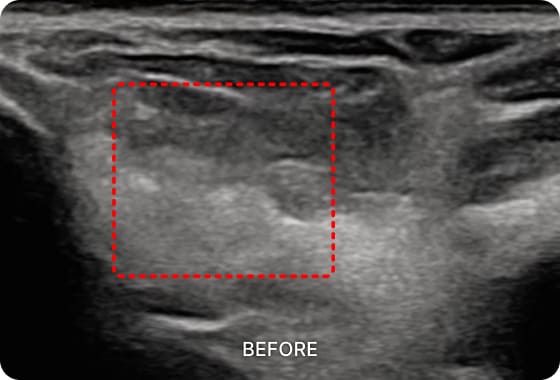

초음파 검사를 통해

수부건초염 통증의 직접적인

원인을 확인할 수 있습니다.

손목에 존재하는 1~6 구획의 건초 상태를

진단하고 정확한 부위를 치료하여 손목과

손가락 통증을 해결합니다.